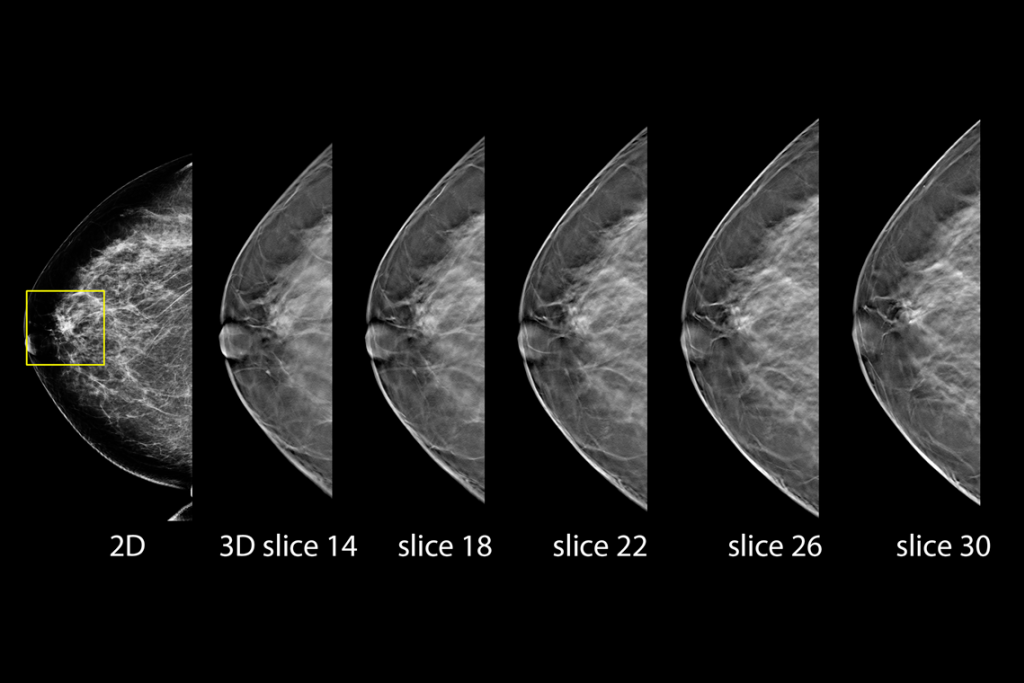

Clinical Images